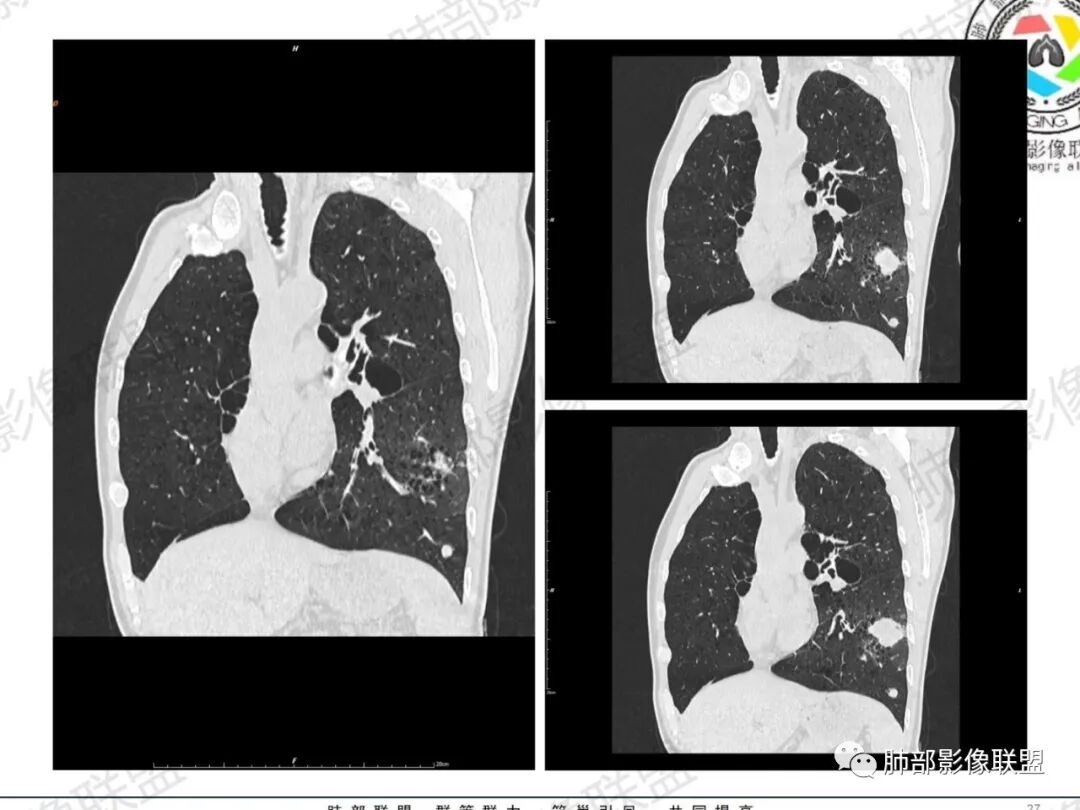

一切∮随缘:左肺下叶不规则肿块,边缘光滑,平直,局部彭隆,分叶,近端支气管堵塞,远端与胸膜相贴,平扫密度尚均匀,增强后不均匀强化,内部可见低密度坏死,胸膜下多发肺气肿,伴双肺散在光滑小结节,实验室肿瘤标志物高,考虑恶性:神经内分泌癌(大细胞),腺癌,鳞癌。

琦遇:恶性没有问题,肺气肿底子、病灶分叶、少许毛刺、叶间胸膜凹陷、部分边缘可见清晰的GGO、胸膜牵拉凹陷、局部胸水、近端支气管截断、部分支气管被推移、占位效应明显、强化特点为不均匀强化、内部有少许沼泽样低强化区,强化部分轻中强化为主、余肺可见转移性结节、左肺上叶似为囊腔型腺癌一枚,肿瘤标志物提示非小、神经内分泌,综合分析考虑大神泌、腺癌、腺鳞癌、鳞癌  同时左肺上叶囊腔型腺癌  肺转移

蕊:中老年男性,吸烟史,肺气肿背景,左肺上叶类圆形肿块影,边界清晰,边缘凹凸不平,有分叶,支气管进入阻断,临近胸膜栽赃,整体病灶膨隆,局部周围可以清晰ggo,临近叶间裂内凹,轻度强化,并可见多个低密度区,坏死可能,界线不清;肺内多结节,边缘光滑,考虑恶性伴转移,鳞癌、腺癌

傅昌瑜:中老年男性,肺气肿背景,右胸背疼痛1周。CEA、NSE、CYFRA—211升高。左上肺混合磨玻璃结节,内见较多空泡和扩张支气管。左下肺胸膜下肿块,边缘较光滑,深分叶,似有血管进入,与支气管关系不清,内见不均匀强化,见沼泽地样坏死,有胸膜栽赃。另两肺多发圆形小结节。考虑恶性并肺内转移,多原发可能性大,左上肺腺癌,左下肺病理难以判断,小细胞癌?鳞癌?

小锁:中老年男性,肺气肿背景,右胸背疼痛1周。CEA、NSE、CYFRA—211升高。左上肺混合磨玻璃结节,边界清楚,内见较多空泡。左下肺肿块,边缘清楚,深分叶,有血管和支气管进入,胸膜凹陷。另两肺多发圆形小结节。考虑双发原位癌,左上肺腺癌,左下肺大神泌或腺鳞癌可能,肺内转移。

蓝天白云:中年男性,肺气肿背景,左肺下叶肿块,边缘膨隆,有分叶,内有湖泊样坏死,有轻中度强化,局部胸膜栽赃,收缩力不强,周围见肺气肿征象。左肺上叶混合磨玻璃影,边界清楚,考虑都是恶性,左上肺iac,左下肺腺鳞癌,或大细胞肺癌可能。两肺多发结节,考虑转移

毛勤香:老年男性,肺气肿背景,左肺下叶肿块,分叶,边缘光滑,土豆块样,细支气管闭塞,增强轻度不均匀强化,似有坏死,左肺另见多发结节,淋巴结未见明显肿大,恶性确定,吸烟史,鳞癌破坏力强,侵袭力差,多原发的一般很少多于3个,故排后,首先考虑神经内分泌癌,局部血管穿行,鉴别淋巴瘤

周太狼:中年男性,吸烟、高血压史,肿瘤指标升高,肺气肿背景下,左肺下叶肿块影,分叶、膨隆、未跨叶裂,支气管截断,不均匀强化。另双肺多发结节及磨玻璃影,左肺上叶混合磨玻璃,内可见多发空泡影。整体考虑恶性,肺癌伴肺内转移,左下肺鳞癌?神经内分泌癌?左肺上叶囊腔腺癌?

LCNEC最常见的影像特征包括:(1)肿块发生部位:周围型肺癌为主,少数发生于肺中央。(2)肿块大小及形态。因肿瘤细胞生长迅速常形成较大肿块,因此其体积一般较大,直径常在3~10cm范围内,病灶常为不规则形软组织肿块。(3)肿块边界。多数学者报道大多数肿块边界清晰,边缘呈分叶状,毛刺征及“胸膜凹陷征”少见,认为与该病对周围组织浸润较轻及较少产生纤维瘢痕组织牵拉有关联。(4)肿块密度、强化特点及代谢情况。据文献报道,该类肿瘤因体积较大CT上常见软组织肿块,且多数密度不均匀,内见囊变坏死区,增强后呈轻或中度不均匀强化(可见强化者占75.7%),认为其强化特点与其内部肉眼可见坏死灶和肿瘤较大直径有关。(5)伴随症状及远处转移。该病恶性程度高,侵袭性强,常侵犯邻近结构,如胸膜、心包、邻近骨质或纵隔内组织等,易出现纵隔淋巴结转移,部分发生肺内及远处转移,少数早期可出现广泛远处转移。

LCNEC患者空洞、钙化、阻塞性肺炎、肺不张、积液这些CT特征较少见,少见支气管充气征。